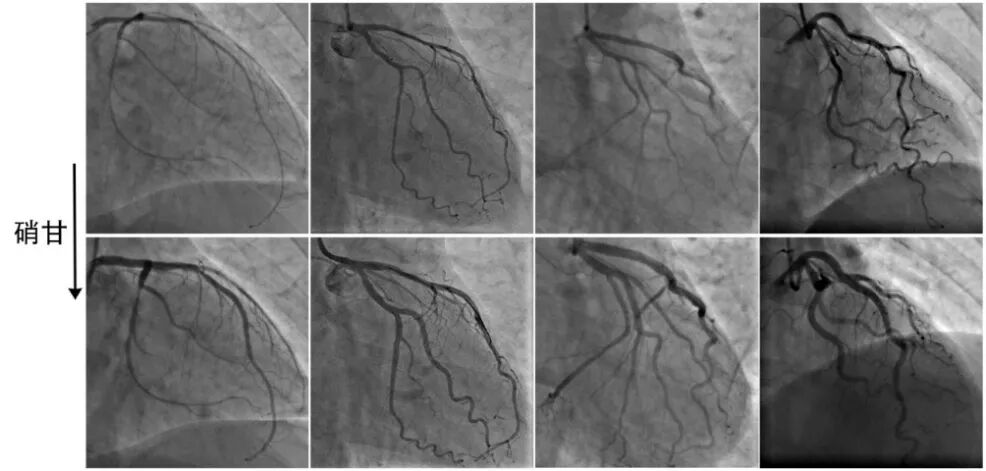

2、弥漫性狭窄

冠脉弥漫性痉挛会出现2种情况:基本正常冠脉发生弥漫性痉挛表现为基本正常的光滑的细长冠脉(如前所述);不均匀斑块基础上发生的弥漫性痉挛则表现为程度不一的弥漫性狭窄,容易和严重斑块导致的弥漫性病变相混淆。

仔细观察,尽管痉挛性弥漫性狭窄的程度不尽一致,但总体基调还是“光滑和对称”(图3),和斑块性狭窄有所不同。

图3冠脉痉挛表现为弥漫性狭窄

3、多支狭窄

多支狭窄和前述的细长冠脉、弥漫性狭窄等具有同样内涵,均强调冠脉痉挛属于整个冠脉的系统性疾病。

单支痉挛或局部痉挛未能识别,病人可能错误的接受介入治疗而不是药物治疗;而多支痉挛未能识别,病人很可能错误的接受外科搭桥而不是药物治疗,显然伤害更大!

多支血管弥漫性狭窄一旦具有以下反常表现,需要警惕痉挛的可能(图4):(1)多支狭窄具有“细小”、“光滑和对称”的特点;(2)缺乏除烟酒外经典的危险因素,与严重冠脉病变不符;(3)平时活动耐量可,与严重冠脉病变不符;(4)心脏大小和功能可,与严重冠脉病变不符。

图4冠脉痉挛表现为多支狭窄[2]